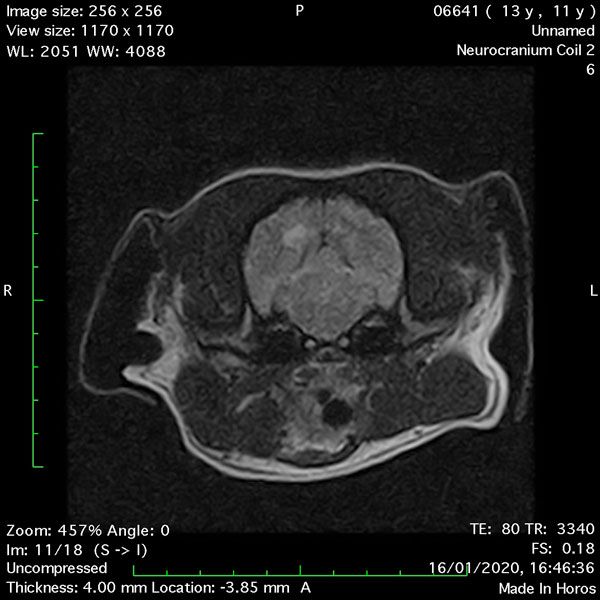

- Transverse T2 – Turbo Spin Echo-S (contrast administered slowly during this sequence) (Figure 2) (Figure 3);

MRI images were viewed in DICOM format (Digital Imaging and Communications in Medicine) (Figures 1-7) and assessed in-house under the guidance of a board-certified radiologist. The series were evaluated for changes in intensity in the T1- and T2-weighted sequences (T1w and T2w, respectively). There was a 4mm x 7mm x 7mm intra-axial, wedge-shaped hyperintense reasonably-well demarcated region in the right cerebrum visible in the T2w images (Figures 2-3). This was consistent with a focal infarct. No contrast enhancement, anatomical abnormality nor space occupying lesion was noted in the T1w sequences (Figure 1, Figure 4). There was no observed pathology on assessment of the FLAIR images (Figure 5).

Figures 1-7: Images obtained with MRI depicted in sequential order and assessed under the guidance of a board-certified radiologist in-house.